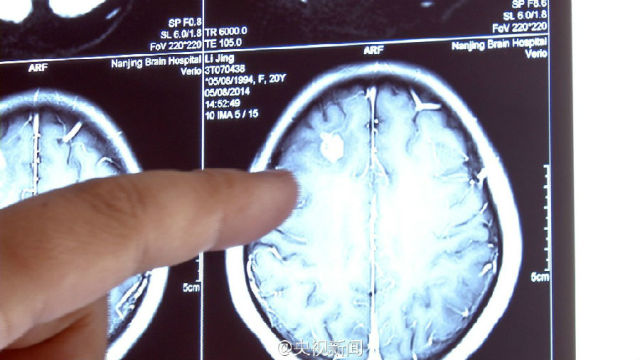

实例一:生吃动物体内长出数千虫子

苏州女孩小严半年来经常头痛、抽搐,医生开颅发现一条30厘米长白色活虫在其脑内游走!此虫是猪肉绦虫的幼虫,小严可能吃了含有绦虫卵的生蔬菜或没熟的肉类,虫卵通过消化道进入血液,再进入脑组织。医生提醒:勿食生食!食物一定要煮熟煮透再吃!(江浙佛教网提示不要食用)